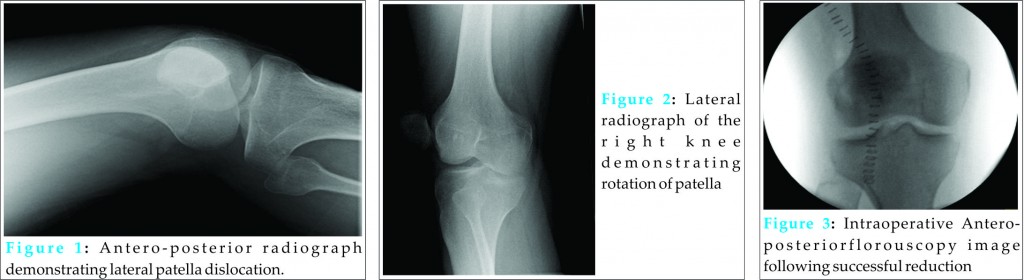

On examination, there was an obvious deformity suggesting lateral displacement of the patella with a sulcus in the skin evident over the femoral groove. Furthermore, the knee was held fixed in 15 degrees of flexion. Due to patient positioning difficulties we were unable to obtain true AP and lateral views on X-ray. The radiographs demonstrated a laterally displaced and a mal-rotated patella in the vertical plane (see Figs. 1 and 2). A manipulation under sedation was attempted unsuccessfully. A further attempt of reduction under a femoral nerve block had again been unsuccessful.

Post-operative radiographs confirm the patella in a satisfactory position in the antero-posterior and lateral planes (see Figs. 3 and 4). The patient was placed in an extension splint for comfort purposes immediately post-operatively. No weight bearing restrictions were applied. Early mobilization was encouraged after 5 days and the patient was referred for early physiotherapy. At 3 months follow-up, our patient had no further episodes of dislocation, full range of knee extension and flexion, and normal patella tracking. A hypermobility assessment at this stage revealed a Beighton score of 2 with extension beyond 10 degrees of both elbows only.